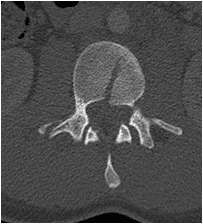

Un chico de 18 años se cayó desde tres pisos. Pérdida casi total de todas las funciones neurológicas por debajo del nivel de lesión con afectación casi total del intestino y la vejiga

El paciente fue operado y el conducto espinal limpiado de todos los fragmentos óseos. La columna vertebral se fijó de lado y la parte trasera para eliminar la inestabilidad.